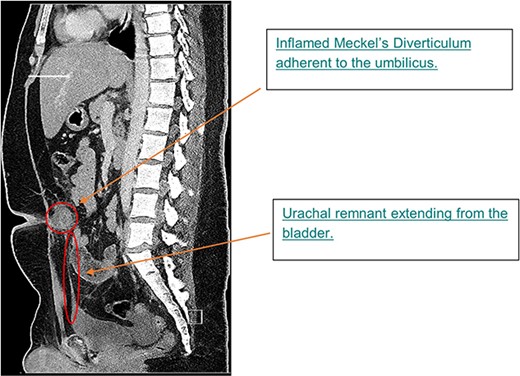

Histopathological assessment of the preperitoneal tissue showed heterotopic gastric tissue with a surrounding smooth muscle layer, previously described in other omphalomesenteric duct remnants [8]. Detailed review of the patient’s pre-operative CT scan revealed a midline urachal remnant (Fig. 3), associated with tenting of the urinary bladder, consistent with a likely vesicourachal diverticulum.

Sagittal image from CTAP at admission; CT showing inflamed MD at level of umbilicus and urachal remnant at apex of bladder tracking up to inflammatory mass.